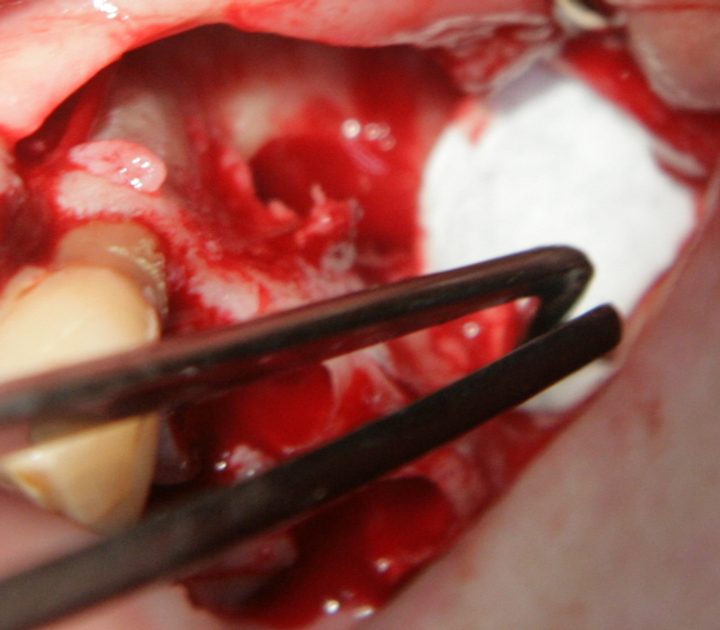

Отворен максиларен синус в началото на интервенцията. Случаят е интересен със следното - твърде атипична форма на трепанационния отвор. На какво се дължи на това - на лошо планиране на оперативния достъп или на нещо друго? Дължи се на факта, че отначало въпросната намеса беше планирана като балонен синуслифт; за съжаление обаче мембраната на синуса се разкъса и надуването на балона стана невъзможно.